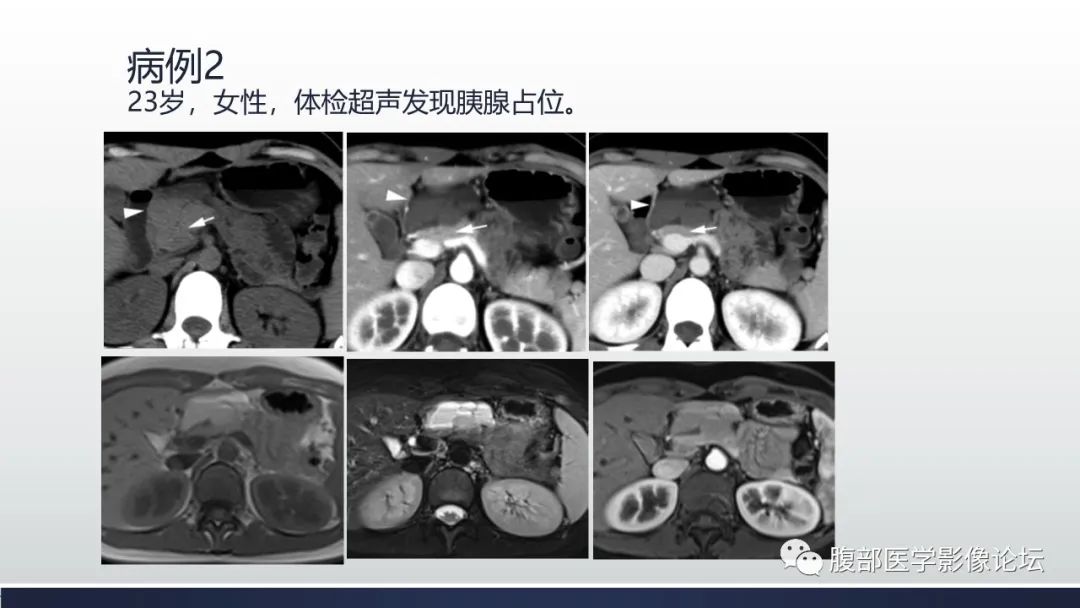

胰腺血管瘤1例CT及MR影像

【病例】胰腺血管瘤1例CT及MR影像-2